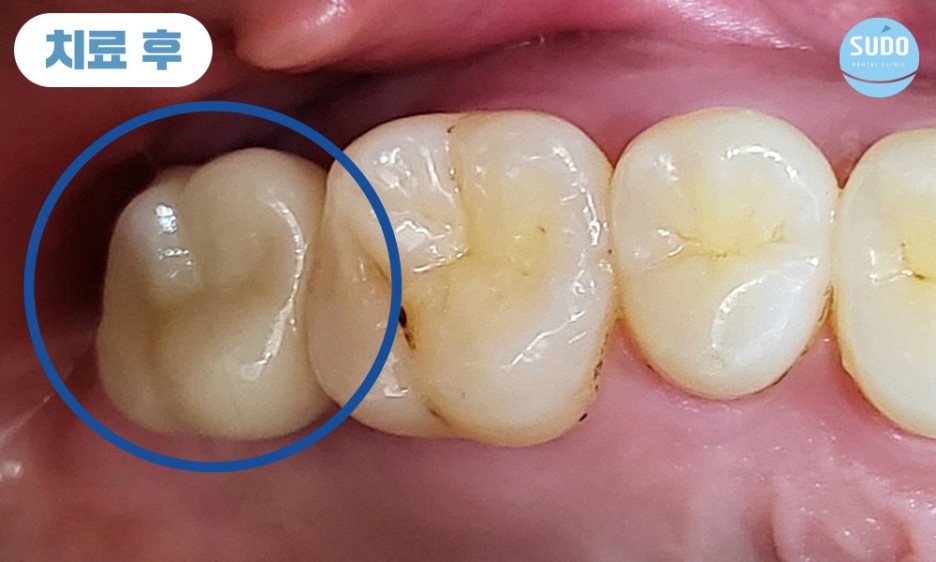

최종 보철물을 장착하고 모든 과정을 마무리한 모습입니다.

임플란트를 단단하게 오랜기간 동안 사용하기 위해서는 인공치근과 잇몸뼈와의 융합이 매우 중요합니다. 잘 융합되어 단단하게 고정되어야 문제없이 사용이 가능하기 때문에 인공치근이 안정적으로 자리 잡을 수 있도록 기다려준 뒤 보철물을 장착합니다.

환자분께서는 잇몸뼈에 단단하게 고정된 임플란트로 편안한 식사에 만족도가 매우 높으셨으며, 주변 치아와의 크기와 색깔도 자연스러움에 감사의 인사를 전해주셨습니다.